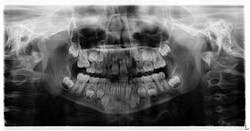

Fig. 4

The following was discussed post-consultation with the orthodontist:

- The mesial drifting of No. 3 was severe enough that it was diagnosed as an irreversible case of ectopic eruption.

- The eruption potential of tooth No. 4 was impeded.

- Leaving the status quo would create a concern for bacterial entrapment and potential abscess; therefore, it was agreed upon that tooth A needed to be removed.

- Upon removal of tooth A, these options were presented to the parents:

- If agreeable to Phase I orthodontics, a palatal expander would be placed and #No. 3 would be distalized so No. 4 would be able to erupt into the arch. This would not necessarily eliminate phase II orthodontics in the future, but the potential for fewer complications would be in the patient’s favor.

- If not agreeable to Phase I, then a space maintainer would be utilized to hold the space as much as possible until a definitive treatment plan could be devised that would be agreeable to the parents. A Nance appliance would suffice to hold the space.